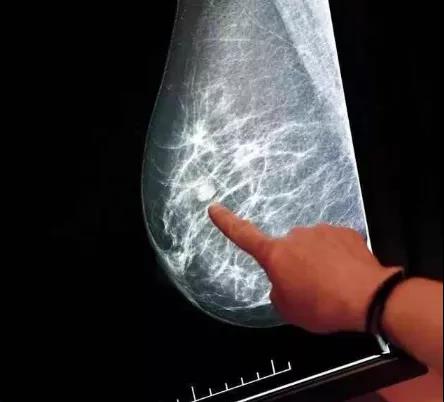

乳房结节是女性常见的症状,包括乳腺增生、肿瘤样结节和恶性肿瘤,为了便于诊断和处理,临床上常用BI-RADS进行分级,以下是分级及处理意见: